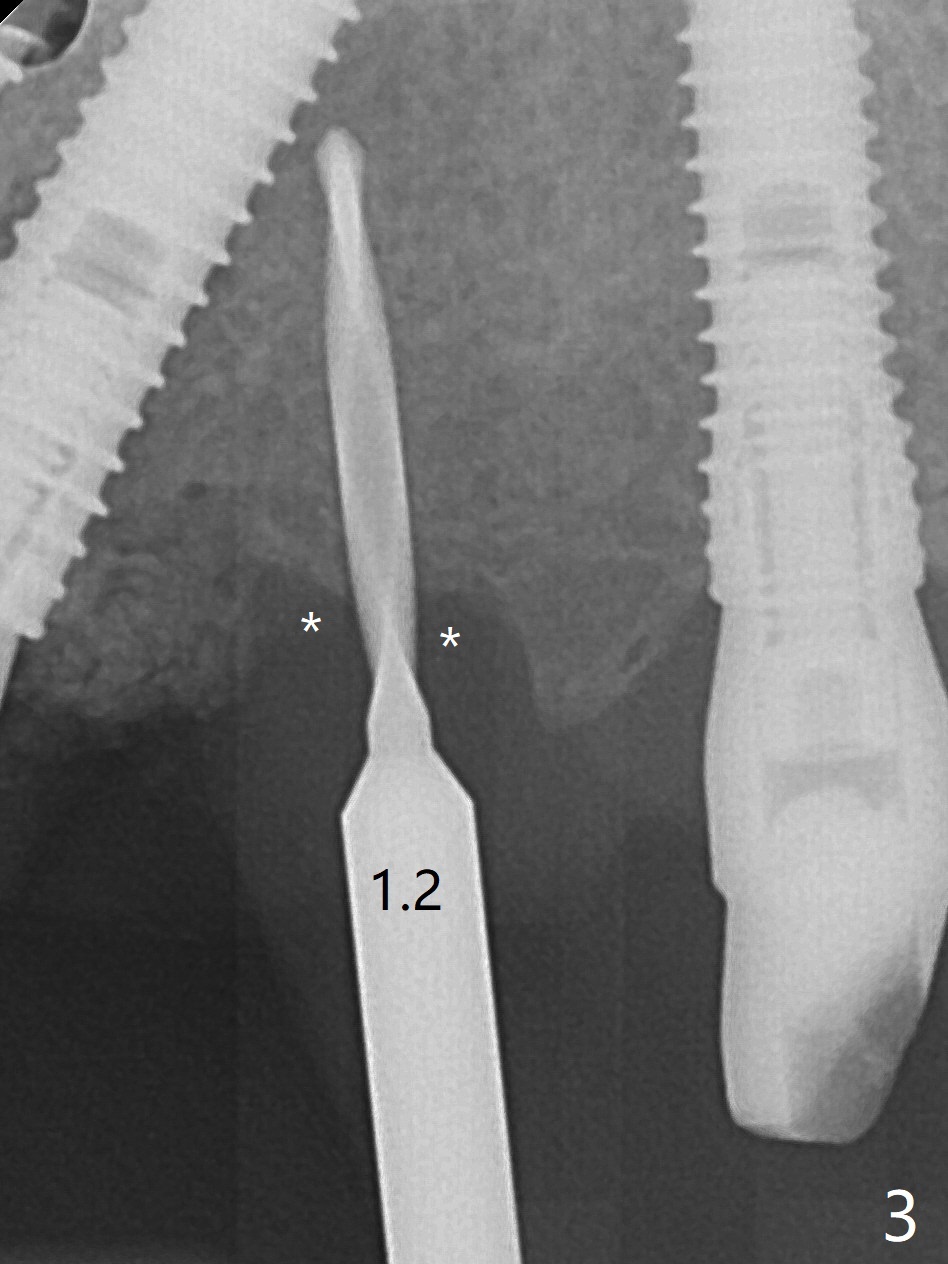

A 48-year-old man returns to clinic with fractured FPD 1 year 5 months post cementation (temp bond, Fig.1,7). It appears necessary to add an implant at #13 site (Fig.2). The narrow ridge is reduced to start an osteotomy (Fig.3 *). After change in osteotomy position and trajectory (Fig.4), a 3x10(4) mm 1-piece implant is placed (Fig.5). With deeper placement of the implant (Fig.6 arrow), cortical bone graft is placed (*).